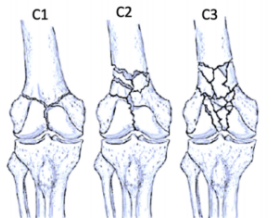

股骨遠端骨折分型

股骨遠端骨折可根據骨折模式、部位和膝關節受累情況進行分型 ,AO/OTA分型常用于對這些骨折進行分類。在每個類別中,骨折可根據復雜性和移位程度進一步分類,對于與全膝關節置換術(TKA)相關的假體周圍股骨遠端骨折,基于骨折移位和TKA股骨假體完整性的Lewis和Rorabeck分型(1997年)是最常用的分型:

A型:關節外骨折

不累及關節面

B型:部分關節內骨折

累及部分關節面但保持一定的關節匹配性

C型:完全關節內骨折

關節面完全破壞